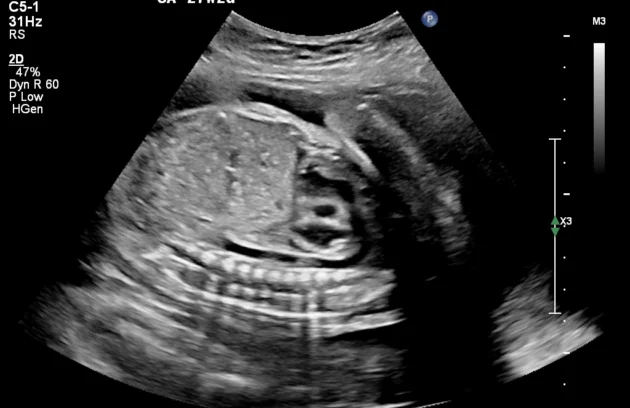

🔹 Anomaly Scan (Level II Ultrasound)

Anomaly Scan is a detailed ultrasound performed during pregnancy (usually between 18 and 22 weeks) to check the baby’s development. It helps detect structural abnormalities in the brain, heart, spine, kidneys, and other organs. This scan ensures your baby is growing normally and helps doctors identify any potential complications early. If you are looking for a reliable anomaly scan in Kathmandu, an early and accurate diagnosis is essential for a safe pregnancy.